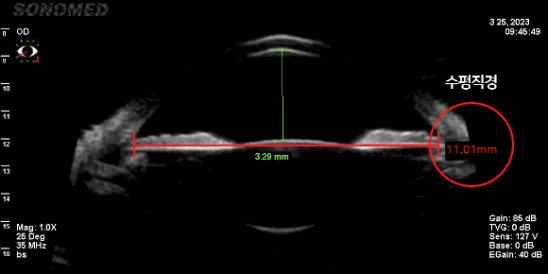

정확한 안구공간 측정

-

렌즈가 삽입될 공간이 충분한지 안구 공간 측정이 정확히 이루어져야 수술 가능 여부, 렌즈 사이즈,

렌즈 회전율을 최소화할 수 있는 렌즈 삽입 위치가 결정됩니다.

평균적으로 수직 직경이 수평 직경보다 길기 때문에 수직형 V-토릭 ICL은 넓은 공간에 여유 있는 사이즈의 렌즈가 삽입되어

렌즈 주변부의 접촉이 없어 렌즈삽입술의 부작용을 방어하고 안정성이 높습니다.-

수평 안구 공간 측정 (11.01mm)

-